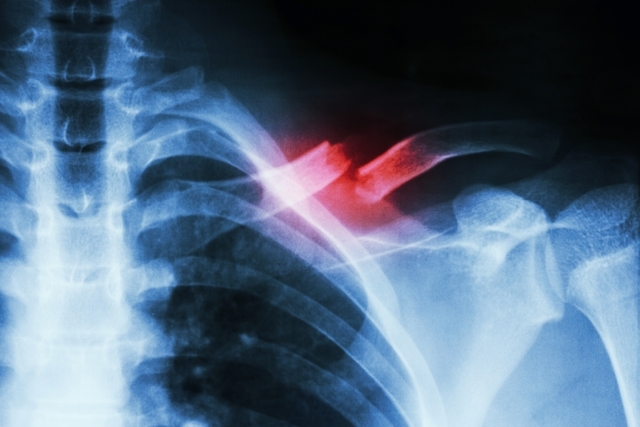

No lugar de dores, meses de internação e sequelas funcionais, as vítimas de traumas ósseos podem contar com um tratamento inovador de reconstrução, reparação e regeneração do tecido ósseo com a ajuda da modelagem 3D e células-tronco. Uma pesquisa de caráter pioneiro em curso na Bahia está viabilizando a recuperação completa do tecido músculo esquelético, redução das dores pós-operatórias, do tempo de internação e dos impactos na área econômica da saúde e social para esse tipo de paciente.

O pioneirismo do projeto — o HUPES é a única unidade autorizada até aqui pelo Ministério da Saúde e pela Comissão Nacional de Ética em Pesquisa (CONEP) a desenvolver essa pesquisa no país – mostra-se, entre outros elementos, pelo recurso à impressão em três dimensões para construir, com 100% de precisão, moldes de ossos, segmentos de ossos ou articulações, a partir de imagens de exames dos pacientes lesionados, informa Daltro. Ele explica que “a modelagem é usada no centro cirúrgico para reparar as estruturas lesionadas, mediante a injeção de células-tronco”. De acordo com o pesquisador e médico, “a impressão em 3D é um avanço, pois sinaliza, exatamente, o que é possível reconstituir e também pode revelar se está faltando material, pois muitas vezes, ficam fragmentos de osso e tecidos, no local do acidente”.

Por conta disso e diante do grande número de acidentes de trânsito, principalmente motocicletas, que resultam em traumas de alta energia e lesão grave de ossos e músculos, os achados científicos do estudo já terão sua aplicabilidade testada via tratamento de fraturas com impressão de moldes em 3D e injeção de células-tronco, num grupo de 12 a 14 pacientes, de idades e sexos variados, dos quais a maioria é formada por adultos jovens vítimas de acidentes. De acordo com o médico, que tem larga experiência em cirurgia ortopédica, os pacientes selecionados já preencheram a documentação para o cumprimento ético da pesquisa, cujos procedimentos práticos começarão a partir do próximo mês de agosto, no HUPES.

Remodelagem de órgãos em 3D

A reconstituição de uma articulação como o joelho, sem a impressão 3D, pode ser feita com uma radiografia, mas não conservará o nível da superfície articular necessária para que a área possa recuperar sua função, pondera Daltro. “Tal inexatidão pode deixar um desnível – mesmo que milimétrico – que estimulará a formação de uma artrose precoce como consequência”, destacou, acrescentando que “quando estamos reconstituindo um segmento funcional temos que ser exatos, que é mais do que precisos”.

“A impressão em 3D dá exatamente a visão do que é possível reconstituir e ainda pode mostrar que está faltando material, indicando o quanto é preciso colocar a mais de osso, que pode variar de 3 a 5 cm. A medida tem que ser exata para cada paciente e cada paciente é diferente do outro”, ressalta o médico. Handerson Leite, que é doutor em saúde pública, revela que “o processo ainda está na curva do aprendizado a fim de encontrar o software e procedimento mais adequados, pois nenhum software de engenharia consegue pegar as curvas humanas que são diferenciadas, então é preciso fazer a conversão com tratamento e cuidados da imagem”.